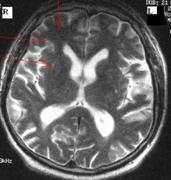

Examenul MRI cerebral efectuat peste doua saptamāni arata aceleasi zone milimetrice de hipointensitate īn T1 si hiperintensitate īn T2 īn substanta alba la nivelul lobulul temporal drept, imediat subcortical.

Localizarea leziunilor de tip IL grupat, imediat subcortical īntr-o zona de granita si aparitia simptomatologiei īn timpul angiografiei sustin existenta unui mecanism hemodinamic. Desigur, acest mecanism este cel mai adesea la originea unor manifestari de tip AIT sau a unui infarct de granita. [2] Īn cazul nostru, nu s-a constituit un infarct de granita ci doar multiple IL īn aceeasi zona, dar aparitia lor are aceeasi semnificatie.

Mecanismul hemodinamic este recunoscut ca fiind un posibil mecanism al producerii IL, īn regiunea centrala a substantei albe emisferice, la limita teritoriului superficial si profund. [3,4,5,6,7] Īn cazul nostru, apar acest tip de leziuni la limita a doua teritorii vasculare, īntr-o zona de granita.